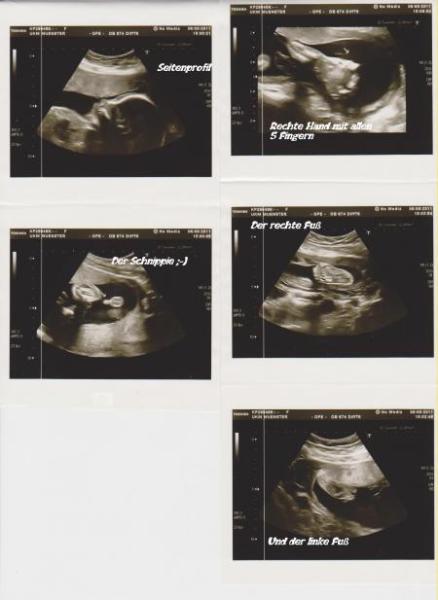

Also Elias Jordan ist ein gerngesunder kleiner Junge,alles da wo es hin gehört,kein Grund an Frühgeburt zu denken oder sich um den Darm Sorgen machen zu müssen. Ich bin erstmal etwas beruhigt,aber er ist jetzt schon sehr groß,der Oberarzt meinte dass in dieser Woche nur 20% der Babys größer ist. Hier mal seine Daten 29cm und 575 Gr. BPD 55,8 mm FOD 76,1 mm KU 207,2 mm AU 183,0 mm FL 41,5 mm (*7 ergibt dass die Gesamtlänge des Babys) Kann nur sagen,hab nicht schlecht geschaut. Hab auch gerade mit den anderen zweien verglichen und meine Jungs werden schon im Bauch immer größer,wo soll das nur hin führen LG Patricia und Elias Jordan inside (23+0)

Bild zu

Guten abend, es freut mich sehr das mit dem kleinen mann alles o.k.ist und krass wie gross er ist!!!! Die bilder sind total schön!!! Wünsche dir einen schönen abend!!! LG